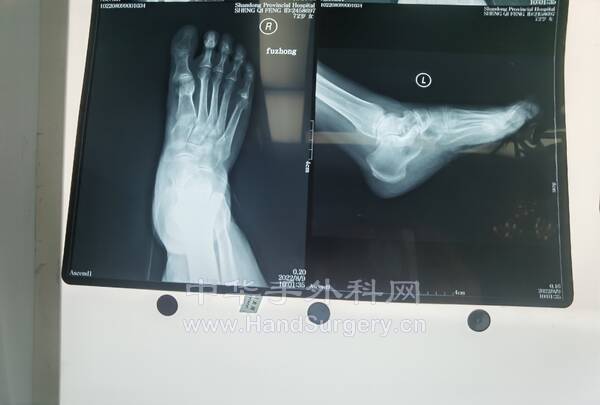

今日参观刘主任踇外翻手术1台,跟刘老师上台手术3台:右足第3趾肿物,右右拇趾肿物,双足踇外翻,刘老师细心教我们很多手术细节,很好的老师!